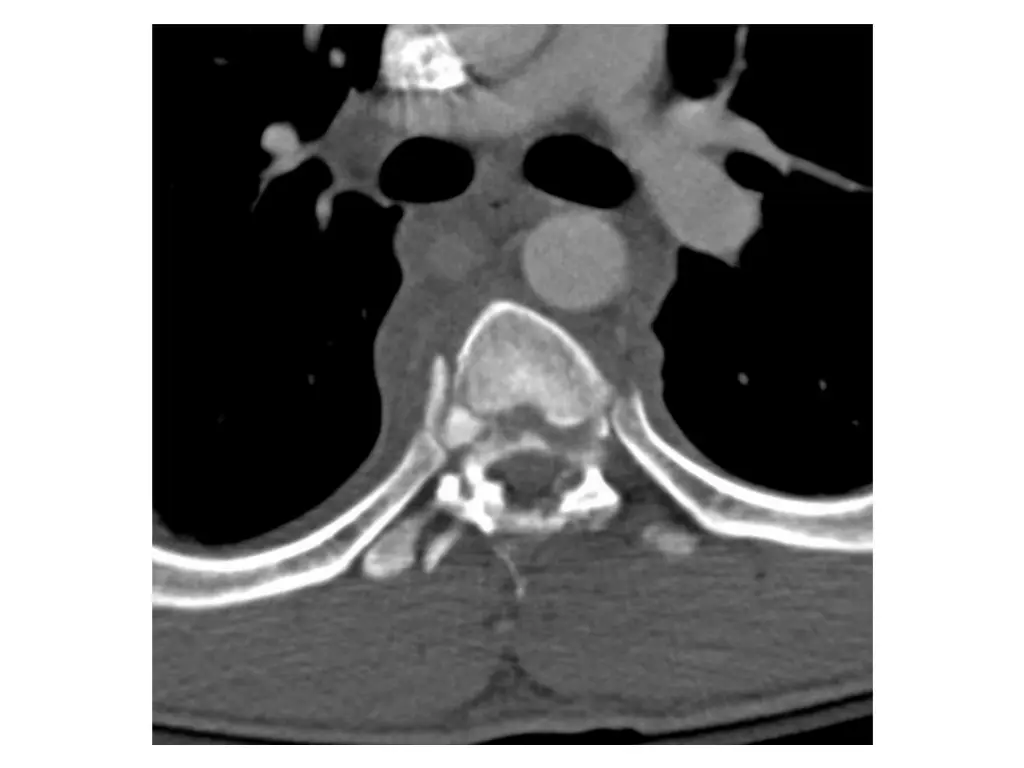

Clinical Hx (Case 1) 22 year old male. Ejected from a vehicle during a high speed single vehicle rollover. Immediate complaints of chest and back pain. Transported to FMC. Hemodynamically stable. No LoC. Injury to thoracic or lumbar spine and associated bilateral pulmonary contusions.

Neurological exam (Case 1) Upper extremity: Sensory: Normal to light touch and pinprick Motor: 5/5 power in all muscle groups Lower extremity: Sensory: Absent sensation Motor: 0/5 power in all muscle groups Rectal: Sensation: Absent Voluntary sphincter tone: Absent Other relevant findings: No sensation to pinprick below costal margin bilaterally. Complete absence of sensation below umbilicus.

Imaging (Case 1) Midsagittal CT scan Parasagittal CT scan Axial CT scan Midsagittal STIR MRI scan